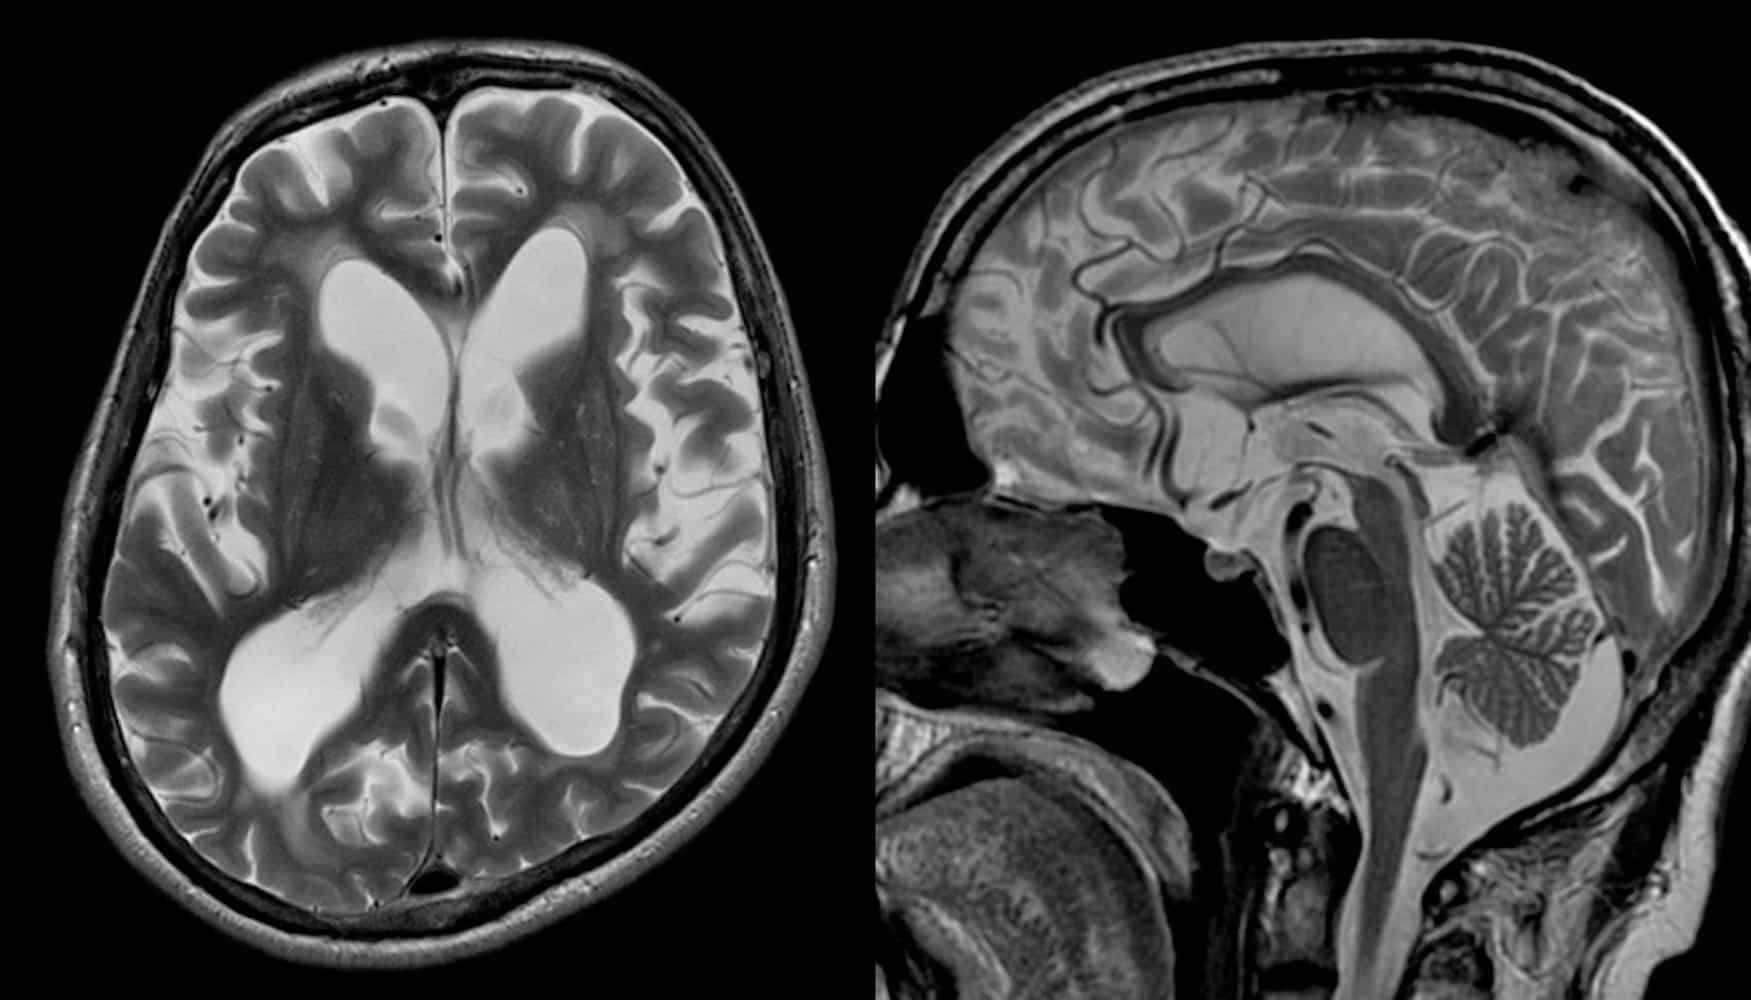

Увеличенные желудочки головного мозга пациента с гидроцефалией на МРТ / © neuroradiologycases.com, Balaji Anvekar

Спинномозговую жидкость впервые обнаружили за пределами мозга   Медицина

Как следует из названия, спинномозговая жидкость циркулирует в головном и спинном мозге. Похоже, теперь в учебники по физиологии придется внести поправки: согласно новому исследованию, спинномозговая жидкость (ликвор) в норме также …